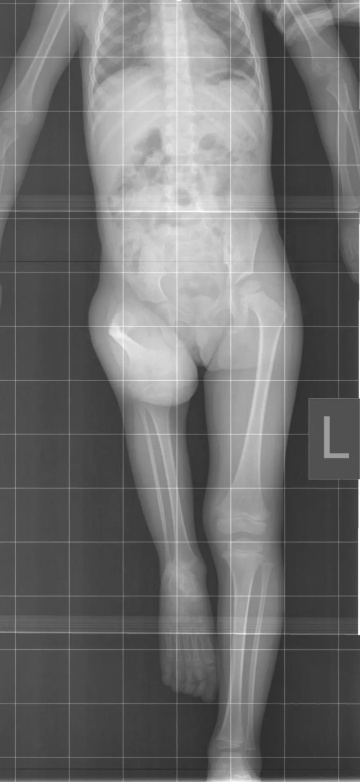

Знакомьтесь – это Серафима, воспитанница Николо-Сольбинского монастыря.

Малышка весёлая, подвижная, очень смышлёная к своим четырём годам. В этом ребёнке столько радости, что даже озорство вызывает умиление. Серафима ещё не осознаёт в полной мере особенностей своего здоровья, но их знаем мы, взрослые. И в наших силах подарить девочке шанс на нормальную, физически активную жизнь. Малышка родилась с деформированным бедром и сильно укороченной правой ножкой. Разница в длине ног увеличивается по мере роста ребёнка, из-за этого Серафима не может самостоятельно ходить. Помогает протез, компенсирующий разницу, но он не дает возможности передвигаться полноценно, а это приводит к другим проблемам: у девочки искривляется позвоночник в грудопоясничном отделе, деформируются внутренние органы. Современная медицина может решить проблемы ребёнка! Помочь Серафиме готовы настоящие профессионалы: курганские врачи из Национального медицинского исследовательского центра травматологии и ортопедии имени академика Г.А. Илизарова.

Малышка родилась с деформированным бедром и сильно укороченной правой ножкой. Разница в длине ног увеличивается по мере роста ребёнка, из-за этого Серафима не может самостоятельно ходить. Помогает протез, компенсирующий разницу, но он не дает возможности передвигаться полноценно, а это приводит к другим проблемам: у девочки искривляется позвоночник в грудопоясничном отделе, деформируются внутренние органы.

Современная медицина может решить проблемы ребёнка! Помочь Серафиме готовы настоящие профессионалы: курганские врачи из Национального медицинского исследовательского центра травматологии и ортопедии имени академика Г.А. Илизарова.